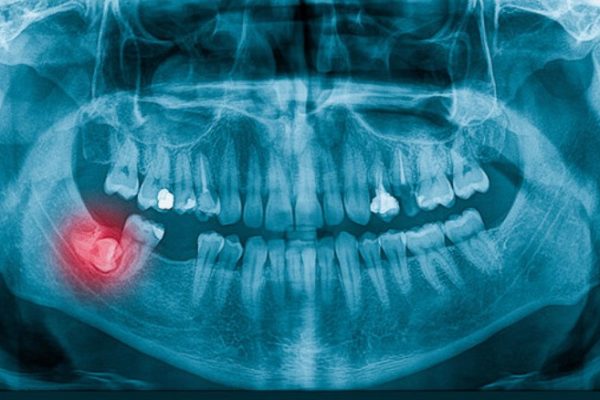

Tìm hiểu mọi điều về răng khôn mọc ngầm Răng khôn (còn gọi là răng hàm số 8 hay wisdom teeth) là chiếc răng mọc sau cùng trong hàm, thường xuất hiện ở độ tuổi ...